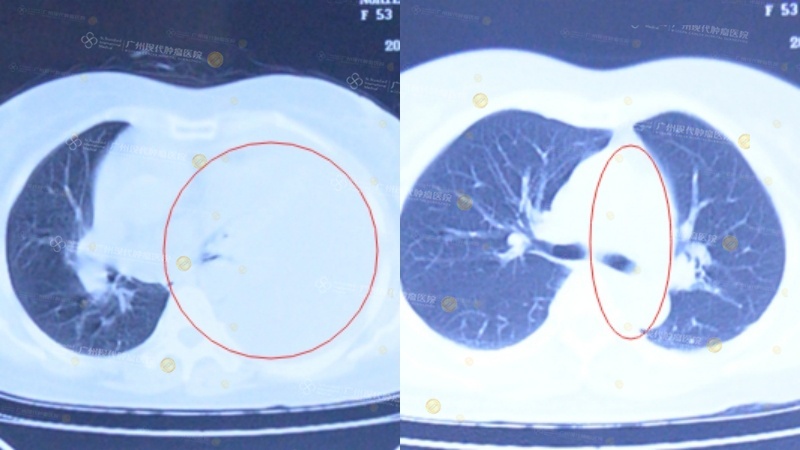

Tháng 9/2014, bà Nghiêm được chẩn đoán mắc ung thư phổi. Sau khi điều trị tại bệnh viện địa phương ở Việt Nam nhưng không đạt hiệu quả, bà đã đến Bệnh viện Ung bướu St.Stamford Quảng Châu. Kết quả kiểm tra khi nhập viện cho thấy bà mắc ung thư biểu mô tuyến vảy kém biệt hóa ở phổi trái, kèm di căn màng phổi và hạch trung thất. Sau khi được điều trị bằng phương pháp vi xâm lấn tổng hợp, tình trạng bệnh đã cải thiện rõ rệt. Từ khi kết thúc điều trị đến nay, sức khỏe của bà luôn duy trì ổn định. Hiện bà đã chống ung thư thành công được 11 năm.

(Trái) Trước điều trị, vùng màu trắng là dịch màng phổi; (Phải) Sau điều trị, dịch màng phổi đã biến mất